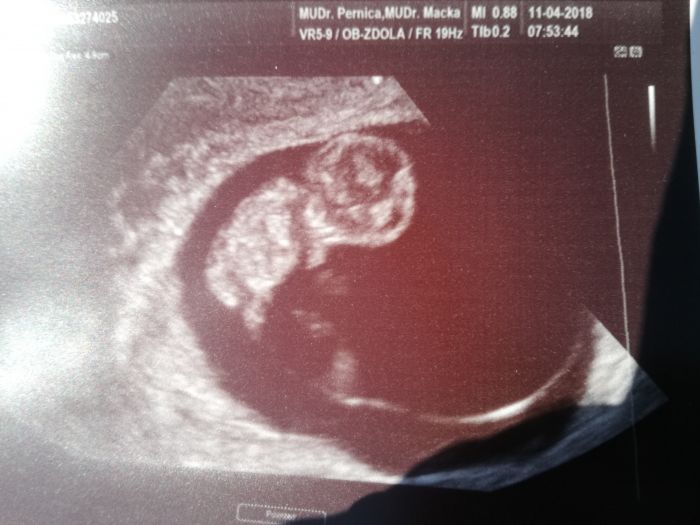

Ahoj holky, tak my za sebou dnes uz taky 2. kontrolu, vychazi mi to na 9+1 dnes. Dnesni kontrola uz byla soucast screeningu, u nas jsem musela byt objednana, v 7h obyc. UZ a pak odbery a dalsi velky UZ mam objednanany za 3 tydny, i s tatinkem prej

uz ten dnesni UZ byl fakt moc hezkej

prdolka mala

jak uz se to tam smrdlalo